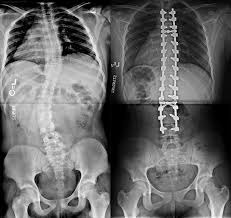

Imagen de rayos X de una escoliosis antes de la cirugía (imagen izquierda) y después de cirugía por vía posterior clásica con tornillos y barras metálicas (imagen derecha).

La columna operada mediante la técnica clásica queda rígida, no se puede doblar, el crecimiento del tronco del paciente se ve limitado durante el crecimiento y una vez se ha completado la fusión, el resultado es irreversible.